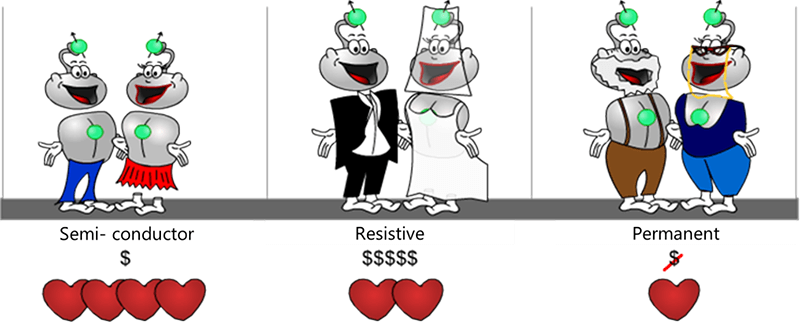

There are three basic classifications of magnets used in MRI. Permanent magnets, resistive magnets and superconductive magnets. Each has its own advantages and disadvantages. Let’s look at each individually.

Permanent magnets are limited in magnetic strength, usually having a magnetic field strength of approximately 0.5 T. These limitations led builders to select other methods to obtain intensities higher than 0.5 T.

The weight of this type of magnet can reach several hundred tons. The prior restriction in terms of size is consistent with a magnet that is very heavy. A permanent magnet that can provide a field of 1 T can easily weigh 300 tons. This evidently imposes severe measures to be taken for the premises housing these machines. Another restriction with a permanent magnet is that they are not very homogenous. As we have seen before, we must have the most homogeneous magnetic field possible in order to obtain a good MRI image.

Again, Permanent magnets are not very powerful. As a result of the restrictions we talked about, a permanent magnet cannot create strong magnetic fields. Builders prefer selecting other methods to obtain magnetic field intensities higher than 0.5 T. This kind of magnet does allow for an open magnetic field and it does not require much consumption of power.

The open style of this magnet is beneficial for claustrophobic patients as they will feel less enclosed in a machine with openings on the sides. They may allow for the patient to turn their head and look out, depending on the examination. They may allow more room for obese patients or allow a family member to sit next to the scanner and hold the patient’s hand. One must be aware, however, that an open MRI may be closer to the face to make up for the open sides.

The next type of Magnet used in MRI is the Resistive magnet which is characterized by a copper wire coil.

Resistive magnets have a homogenous field. One of the advantages of this type of magnet is that it provides magnetic fields of good homogeneity that can be used in MRI. These magnets are used in all MRI machines to generate gradients. Resistive magnet, like permanent magnets, have a weak field. Also, electric consumption by resistive magnets is very high. This is why they are generally not used to create the principal field of a whole-body MRI beyond 0.5 T. This type of magnet is nevertheless used in MRI to create magnetic field gradients.

Resistive magnets are huge energy consumers. This is the major disadvantage of this type of magnet. As we said earlier, the intensity of the magnetic field is proportional to the intensity of current passing through the coil. Unfortunately, its resistivity results in a very low energy yield. This is why this type of magnet is very rarely used in MRI to create an intensity higher than 0.5 T. That brings us to superconductive magnets. This type of magnet is the most common type of magnet in use today in MRI. It is similar to the resistive magnet In that there is a copper wire coil.

The super conductive magnet is nearly homogenous. Homogeneity is the biggest advantage of of the superconductive magnet. They are thus frequently used to generate the principal magnetic field (especially beyond a certain intensity). Superconductive magnets are very powerful and can provide very high intensities. For magnets stronger than 0.5 T, this is the type of magnet used. Superconductive magnets range in energy levels, or magnetization levels. The most common strengths used in medical imaging is 1.5T or 3T, but there are magnets in used today that are as strong as 8T or even 10T.

To summarize the different types of magnets, let’s use a metaphor to better understand the differences and similarities. Consider the life of a couple at different stages of life. The superconductive magnet is represented by the couple during the majority of their marriage, the resistive magnet during the early stages of a marriage and the permanent magnet by the older couple nearing retirement.

In the beginning of the marriage, there is palpable passion but that requires input to maintain because of expenses (jewelry, dresses, a house, children, etc…). Thus, even though resistive magnets offer more advantages in use than permanent magnets, they are high energy consumers. Finally, passion in the young couple is at its maximum. This requires some, but not excessive maintenance costs (flowers, a cinema, restaurant…). The electromagnet provides the best advantage/consumption ratio.

In the final stages of marriage, as the couple gets older and their children are grown and no longer in the house, the couple is comfortable with each other, they are committed and just enjoying their lives. Little effort is needed to maintain the commitment, little energy is required, like the permanent magnet.

There are 3 main types of magnets: Permanent magnets are used for low field intensity MRI systems (less than 1 T), resistive magnets which are generally NOT used to create the main magnetic field and Superconductive magnets, or high-field magnets used in MRI systems over 1 T.